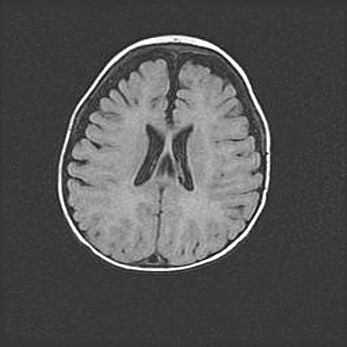

Сообщающаяся гидроцефалия. Кистозная энцефаломаляция головного мозга.

Возраст: 3 месяца 4 дня

Вес: 3100 г

Пол: женский

Окружность головы: 34 см

Срок гестации: 31 неделя

Кистозная энцефаломаляция головного мозга - одна из форм поражения головного мозга в детском возрасте. Характеризуется возникновением множественных и распространённых кист в коре, белом веществе и подкорковых образованиях головного мозга у плодов, новорождённых и детей раннего возраста. Развитие кистозной энцефаломаляции связано с внутриутробной асфиксией и гипотонией, родовой травмой, тромбозом синусов, пороками развития сосудов, инфекциями, сепсисом и другими причинами. Наиболее значимые инфекционные агенты: вирусы простого герпеса, цитомегалии, краснухи, токсоплазмы, энтеробактерии, золотистый стафилококк и другие.